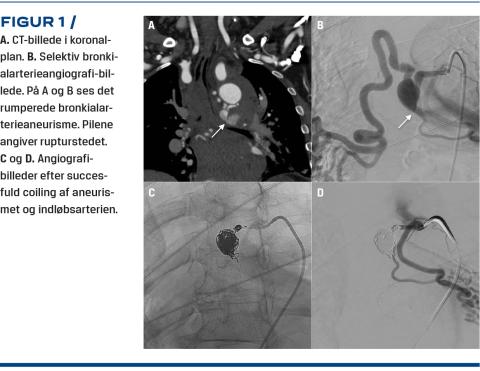

Den tentative diagnose var efter ankomsten fortsat AKS, men fordi patienten havde smerteudstråling til ryggen og hypotension, blev der foretaget akut CT-angiografi for at udelukke aortadissektion, inden man påbegyndte AK-behandling. CT-angiografien viste hæmomediastinum på usikker baggrund. Efter konference med den radiologisk vagthavende på både stamsygehuset og Rigshospitalet viste det sig, at der var tale om et rumperet BAA (18 mm i diameter) udgående fra højre bronkialarterie. Yderligere sås der et hæmatom langs aortas forløb (Figur 1). Patienten blev overflyttet til Rigshospitalet med akutlægeberedskab. Forud for dette blev blodtrykket stabiliseret alene på væskebehandling. På Rigshospitalet blev der udført bronkialarterieangiografi, som viste et BAA i højre bronkialarterie.

Aneurismet blev udfyldt med coils, og indløbet blev lukket ved anlæggelse af en mikrovaskulær plug (MVP) og en enkelt coil.